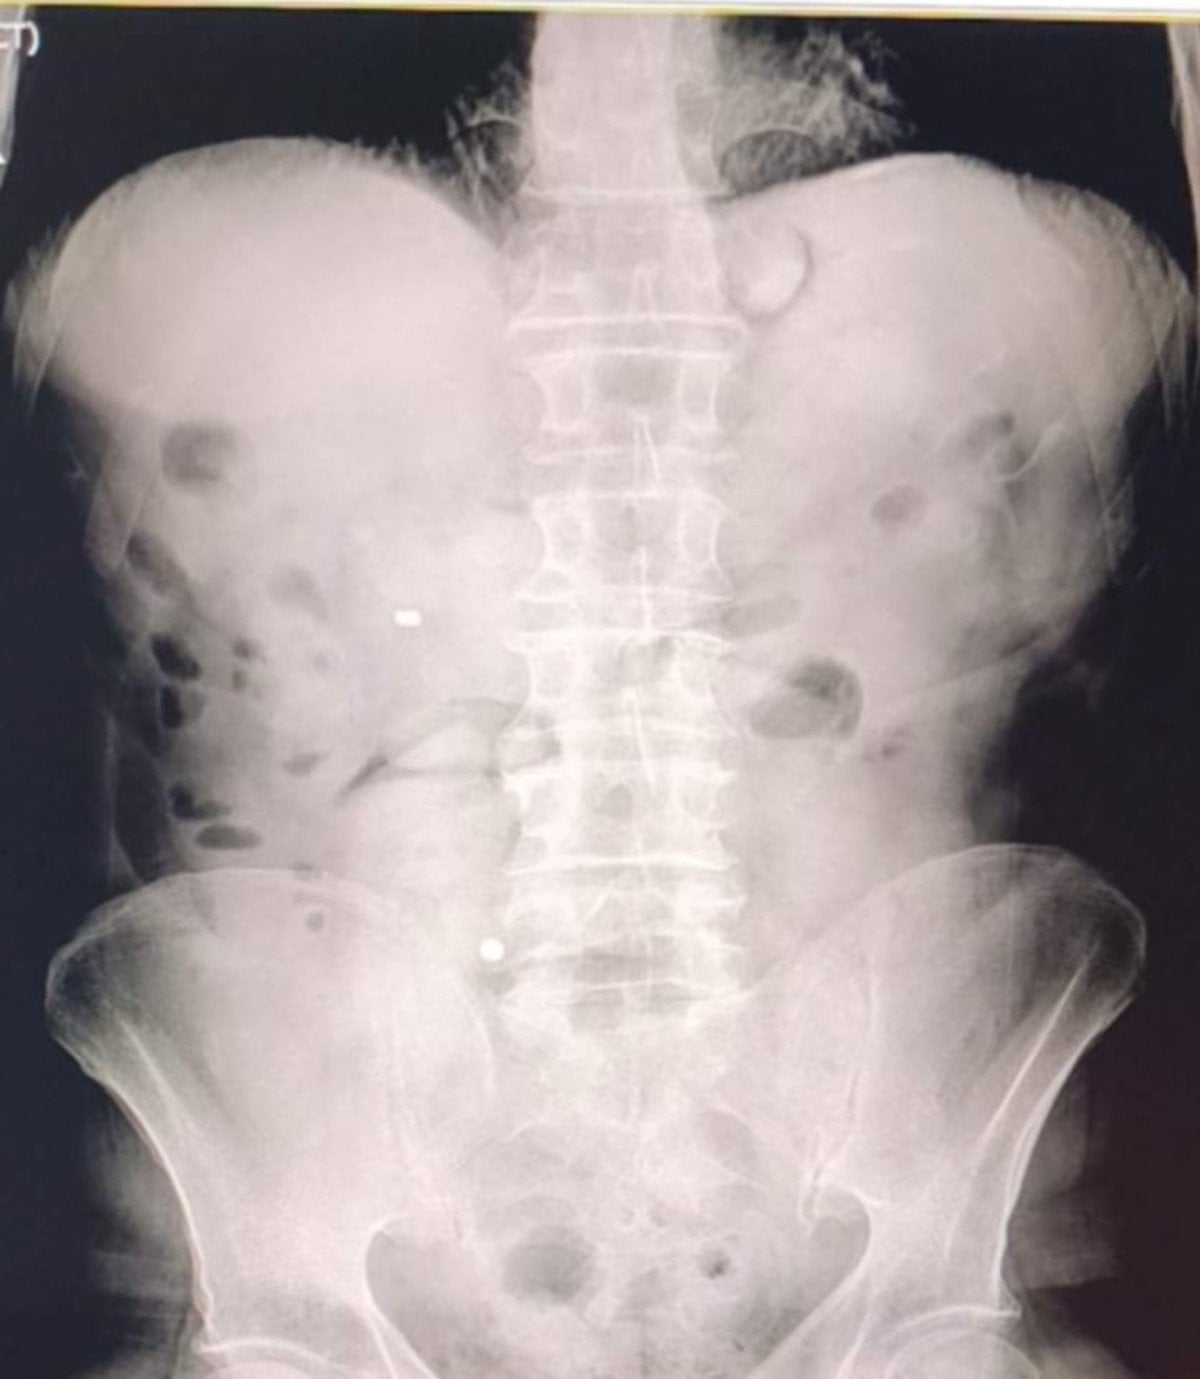

Şüphelilerin hastanede yaptırılan kontrolleri ve çekilen röntgen filmleri sonucunda mide ve bağırsaklarında çok sayıda uyuşturucu madde içeren kapsül bulunduğu tespit edildi.

Hastanede kontrollü şekilde gözetim altında tutulan şüphelilerden tıbbi müdahaleler neticesinde toplam 93 parça halinde 1 kilo 70 gram metamfetamin ele geçirildi.